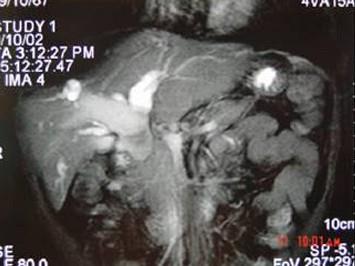

问题 女,35岁,右上腹痛一月,黄疸进行性加重,AFP阴性,消瘦乏力,影像检查如图,最可能的诊断为 ( )

选项 A、原发性肝癌 B、肝血管瘤 C、胆管癌 D、局灶性脂肪肝 E、肝转移癌

答案 C